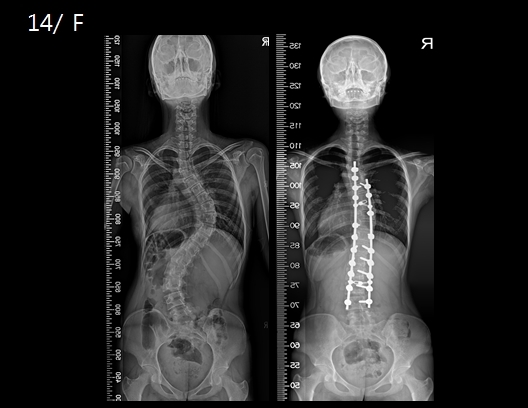

척추측만증은 허리가 C나 S자형으로 휘어지는 척추의 변형으로 골반이나 어깨의 높이가 서로 다르거나 몸통이 한쪽으로 치우쳐 보이는 것이 특징이다. 신체검사 상 5~7도, 엑스레이 검사 상 10도 이상이면 척추측만증으로 진단한다. 척추측만증은 진단이 늦어지거나 제때 치료하지 않고 방치하면 척추는 더욱 휘어지고 심한 변형이 발생하게 된다. 대부분 좌우 어깨 높이가 확연히 차이가 나거나 한쪽 등이 튀어 나왔을 때 척추측만증일 가능성이 높다.

40~50도 휘어진 경우 몸의 성장 정도에 따라 수술이 필요할 수도 있다. 나이가 어리고 몸의 성장이 한창인 경우에는 만곡의 진행속도에 따라 수술을 시행할 수 있지만, 성장이 멈춘 경우(15~16세 이상)에는 변형이 진행될 가능성이 적어 몸의 균형이 잘 맞는다면 수술이 필요하지 않다. 보통 50도 이상 휘어진 경우 수술이 필요하다. 척추 변형이 큰 경우에는 성장이 끝나고 성인이 되어서도 일상생활에 지장이 큰 경우 수술로 휘어진 척추를 교정해 줘야 한다.